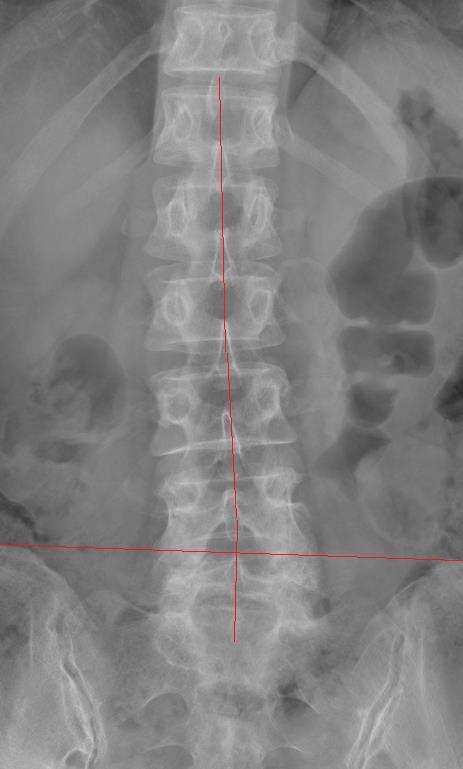

65세의 척추 전방 전위증 환자의 사진입니다.

좌측 장골의 위치가 낮고 척추의 역s자 모양의 측만도 보입니다.